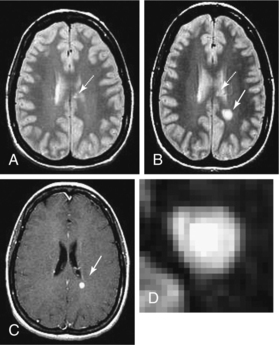

Contrast enhancement in CT and MRI suggests inflammation but is more accurately a measure of leakage of moderate-size molecules across the damaged tight junctions of the CNS endothelium. The enhancement pattern (size, shape, solid versus ring) may be variable within and more so between individuals, which reflects a heterogeneous pathology. Ring enhancement, for example, may suggest a more severe pathology. Fig. 31-10 demonstrates the development of a T2-weighted hyperintense lesion by serial MRI. The correlation between the pattern of enhancement, the underlying pathology, and the clinical course in given individuals may not be straightforward. Monitoring serial MRI studies with enhancement helps to identify agents that may be active against the early inflammatory stage of MS.170

Figure 31-10 Development of a T2 hyperintense lesion by serial magnetic resonance imaging. A, Case of relapsing multiple sclerosis with low T2 hyperintense lesion burden, including chronic lesions in the corpus callosum (arrow). B, One month later, a new T2 hyperintense lesion develops in the left parietal-occipital white matter (solid arrow), whereas the corpus callosum lesions remain stable (dotted arrow). C, Corresponding enhancement in acute lesion (arrow) from blood-brain barrier breakdown and concurrent inflammation. D, Exploded view of the new lesion showing the complex structure, centrally hyperintense, most likely from mixed pathology including demyelination, matrix including glial change, and, importantly, axonal degeneration. The intermediate black ring may be a zone of macrophage infiltration, and the outer ring is likely from edema. (From Radiologic Clinics of North America Volume 44, Number 1, January 2006 Copyright © 2006 WB Saunders Company.)